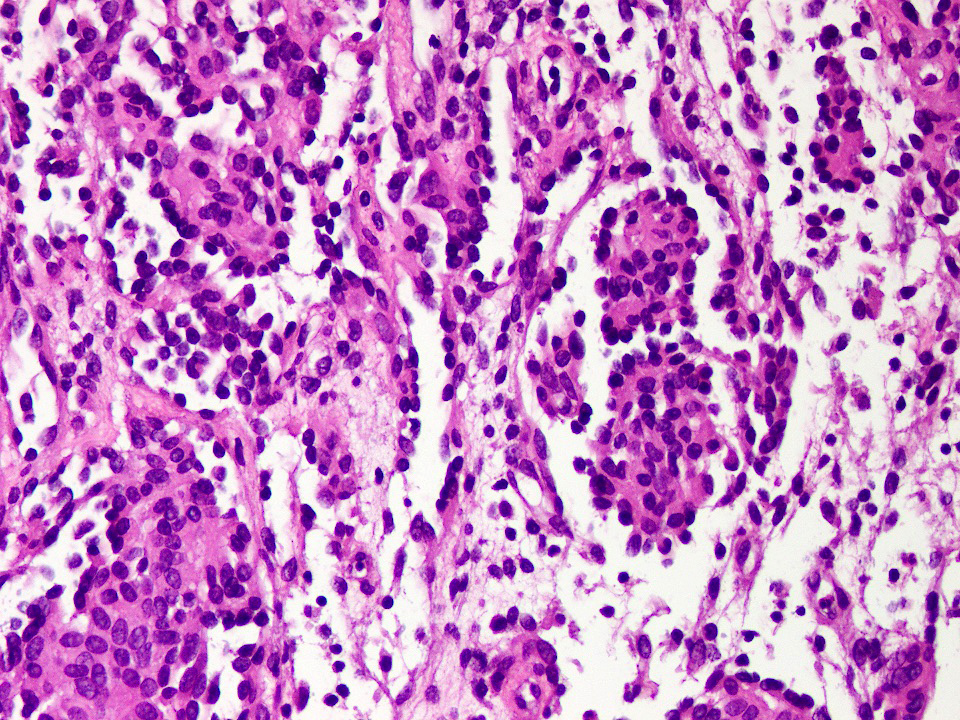

Microscopic (histologic) description

- Poorly circumscribed lesion, infiltrating dermis and subcutis with dissecting planes (Int J Clin Exp Pathol 2010;3:528)

- Composed of elongated arborizing vascular channels that resemble rete testis, hence the name

- Endothelial cells are bland with hobnailed hyperchromatic nuclei

- Nuclear atypia is not seen

- Mitotic figures are rare

- Lesional stroma is fibrotic and shows lymphoid infiltrate (J Med Case Rep 2021;15:69, Int J Clin Exp Pathol 2010;3:528)

- Occasional solid growth may be seen (Stockman: Diagnostic Pathology - Vascular, 1st Edition, 2015)

- In the dermis, vessels may become ectatic and lose retiform appearance

- Occasional cells with cytoplasmic lumina may be rarely seen (J Med Case Rep 2021;15:69)

- Occasionally, intraluminal papillary proliferation may be seen, resembling Dabska tumor (Hornick: Practical Soft Tissue Pathology - A Diagnostic Approach, 2nd Edition, 2018)

Microscopic (histologic) images

A 30 year old man presents with a red to purple plaque involving the right thigh. A punch biopsy through the lesion shows light microscopic features as depicted in the photomicrograph above. Which of the following is the most likely diagnosis in this case?

E. Retiform hemangioendothelioma. The photomicrograph shows a vascular lesion with retiform vessels lined by a single layer of endothelial cells with hobnailing. A lymphoid aggregate is also present. Answers B - D are incorrect because other characteristic essential features of any of the given options, except atypical vascular lesion, are not seen here. Answer A is incorrect because the clinical scenario is not appropriate for a diagnosis of atypical vascular lesion. Therefore, the correct diagnosis is retiform hemangioendothelioma.